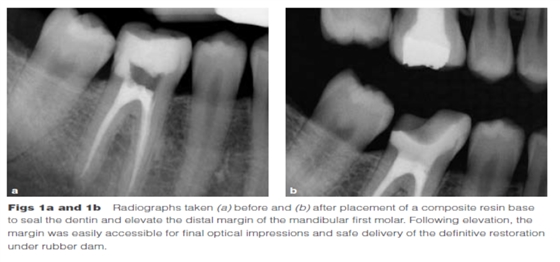

Dietschi和Spreafico在1998年提出了另一種方法,即在間接修復(fù)體的下面放置一個(gè)復(fù)合樹(shù)脂基底來(lái)取代冠向提升邊緣(圖1)。這個(gè)方法即我們所知的齦壁提升術(shù)(DMG)是在橡皮障隔離下完成的?(This procedure,…,is performed under rubber dam isolation following the placement of a matrix.)如今,DME(齦壁提升術(shù))通常與IDS(即刻牙本質(zhì)封閉術(shù))聯(lián)合使用來(lái)促進(jìn)間接粘接修復(fù)體的粘接和齦邊緣的封閉。此外,邊緣的齦上提升,粘接復(fù)合樹(shù)脂基底被用于封閉牙本質(zhì)、加強(qiáng)潛在牙尖?(reinforce undermined cusps),充填倒凹(fill undercuts),以及為嵌體/高嵌體修復(fù)提供必要的幾何形態(tài)。

DME是用一個(gè)改良彎曲的成型片接堆放復(fù)合樹(shù)脂來(lái)提升齦壁高度,使其能夠在修復(fù)過(guò)程中使用橡皮障封閉邊緣,可以在固化前適當(dāng)?shù)囊瞥嘤嗟膹?fù)合樹(shù)脂。DME應(yīng)該在即刻牙本質(zhì)封閉(IDS)之后,在使用橡皮障的條件下,且僅在邊緣可被改良的成型片適當(dāng)隔離時(shí)直接獲得。否則,這個(gè)技術(shù)不能使用。在最終取印前,需要拍攝咬合翼片來(lái)評(píng)估復(fù)合樹(shù)脂在齦邊緣區(qū)域的密合度(有無(wú)懸突或缺陷)。同樣需要仔細(xì)隨訪來(lái)評(píng)估軟組織的健康和是否需要外科手術(shù)干預(yù)。只要可能,在牙髓治療前就應(yīng)通過(guò)DME術(shù)制造假壁,使根管治療更完善(圖2、3)。圖4展示了一個(gè)典型DME術(shù)的適應(yīng)癥。